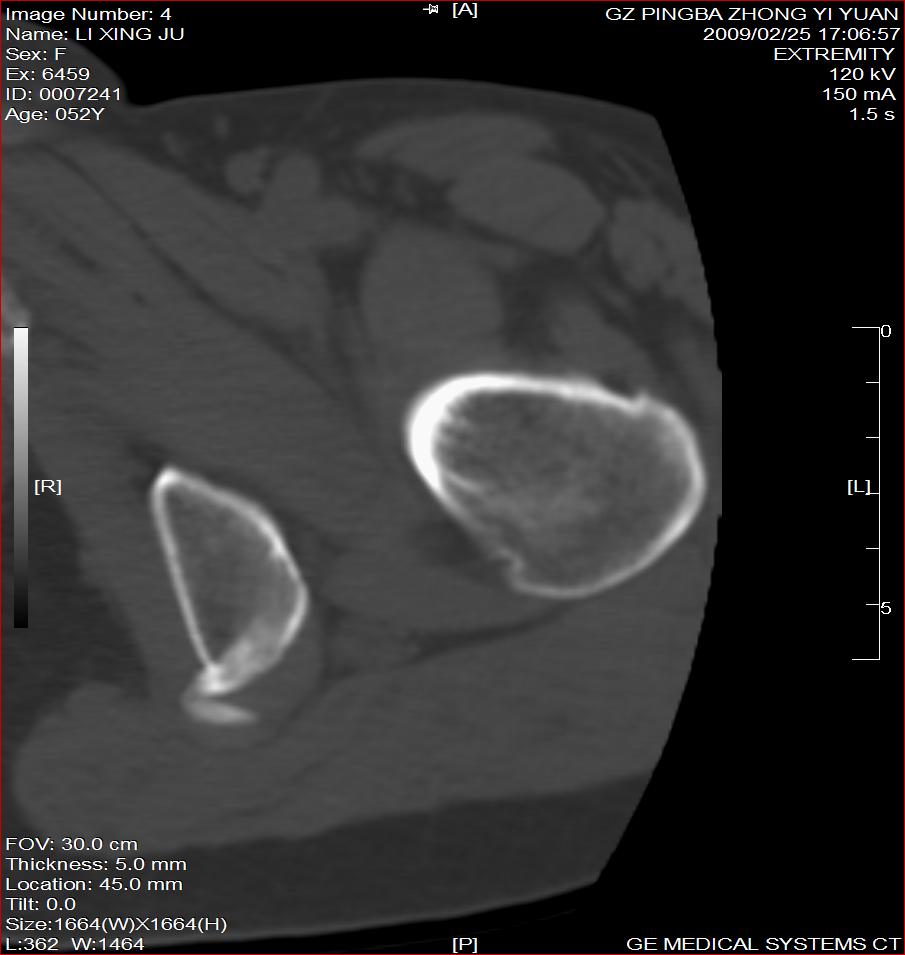

标题: CT18521:左大腿疼痛不适1+月 [打印本页]

标题: CT18521:左大腿疼痛不适1+月

考虑-----股骨骨化性纤维瘤可能性大,不除外---局限性骨纤

考虑:左股骨骨化性纤维瘤

考虑 左股骨骨化性纤维瘤。

考虑:左股骨骨化性纤维瘤。